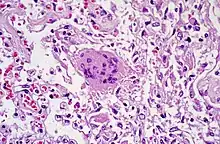

Le diagnostic virologique repose sur la mise en évidence du virus SARS-CoV à partir de prélèvements nasaux, pharyngés, d’expectorations, d’aspirations endo-trachéales, de sang, de selles ou d’urines par RT-PCR ou culture virale. L’excrétion du virus SARS-CoV est assez faible au début de la maladie, elle est maximale environ 10 jours après le début des signes cliniques. Le virus est alors retrouvé dans les sécrétions respiratoires et dans les selles. Une étude portant sur l’utilité clinique des différents tests diagnostiques a montré que l’ARN du SARS-CoV était détecté par RT-PCR dans les sécrétions naso-pharyngée chez seulement 32 % des patients à la phase initiale et dans 68 % des cas 14 jours après le début des signes cliniques (Peiris, Lancet 2003). Une analyse quantitative a montré que la charge virale atteint son maximum 10 jours après le début des signes cliniques. L’ARN viral est détecté dans les selles chez 98 % des patients plus tardivement au cours de la maladie (vers le 14e jour) et dans les urines après le 15e jour. Les tests de RT-PCR restent actuellement assez peu sensibles et il est fortement conseillé de multiplier les examens d’échantillons naso-pharyngés pour améliorer la valeur prédictive du test. Un test de RT-PCR négatif n’exclut pas le diagnostic de SRAS : les échantillons peuvent avoir été prélevés à un moment où la charge virale était trop faible pour être détectée par les tests de laboratoires disponibles.

La présence du virus peut être mise en évidence en inoculant des cultures cellulaires (cellules Vero) à partir d’échantillons de selles, de sang ou de sécrétions respiratoires. Une fois le virus isolé, il faut utiliser d’autres tests (immunofluorescence par exemple) pour identifier le SARS-CoV. L’isolement du SARS-CoV en culture cellulaire doit être réalisé au minimum dans un laboratoire de niveau de sécurité BSL3. Des résultats de culture cellulaire négatifs n’excluent pas le diagnostic de syndrome respiratoire aigu sévère, pour les mêmes raisons que dans les cas de RT-PCR négatives.